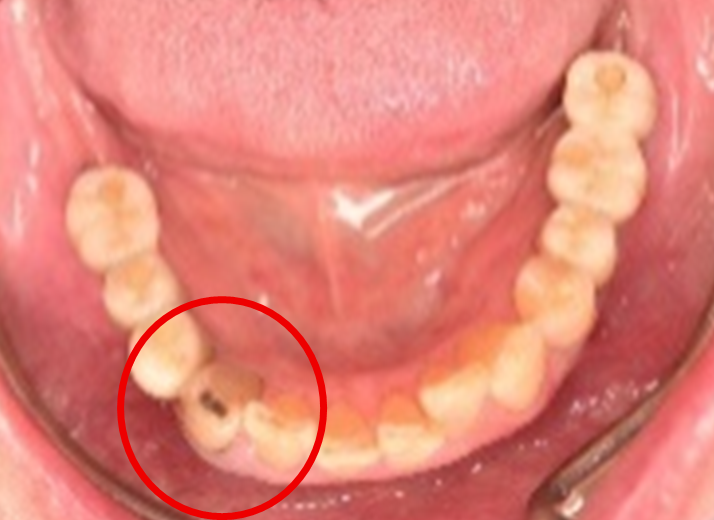

被せ物の中で大きな虫歯になっていました。被せ物を取り除き、神経をとる治療をしました。メタルフリーの治療を希望されましたので、オールセラミックのブリッジを装着しました。

所感

金属を使わない治療を希望されました。体全体の健康のことを考えると、徐々に口の中の金属を減らしていくことは、とても良い事だと考えます。